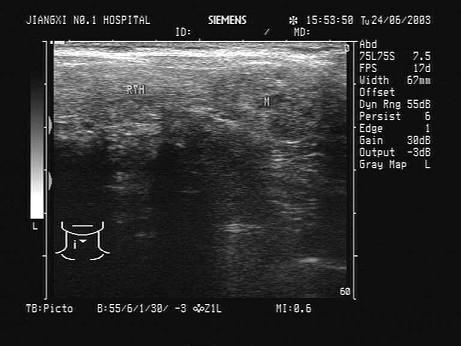

问题 患者发现颈部肿块两年,无明显不适。甲状腺超声见甲状腺肿大回声不均匀,如图。最可能的诊断为?(?)

选项 A.甲状腺癌 B.结节性甲状腺肿 C.桥本甲状腺炎 D.甲状腺腺瘤 E.甲状腺囊肿

答案 B